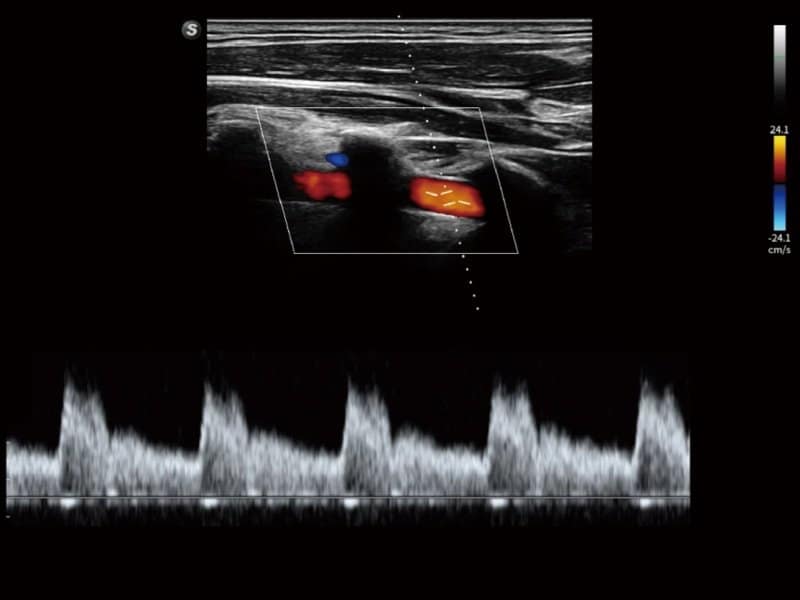

Klinische Bilder

- Kardiologie: Automatische Identifizierung von Herzstrukturen via S-CV (TDI/Messung), Stress-Echokardiographie und MQA zur Bewegungsanalyse.

- Radiologie: Quantitative Beurteilung der Lebersteatose durch ATI, Strain-Elastographie und kontrastverstärkter Ultraschall (CEUS)